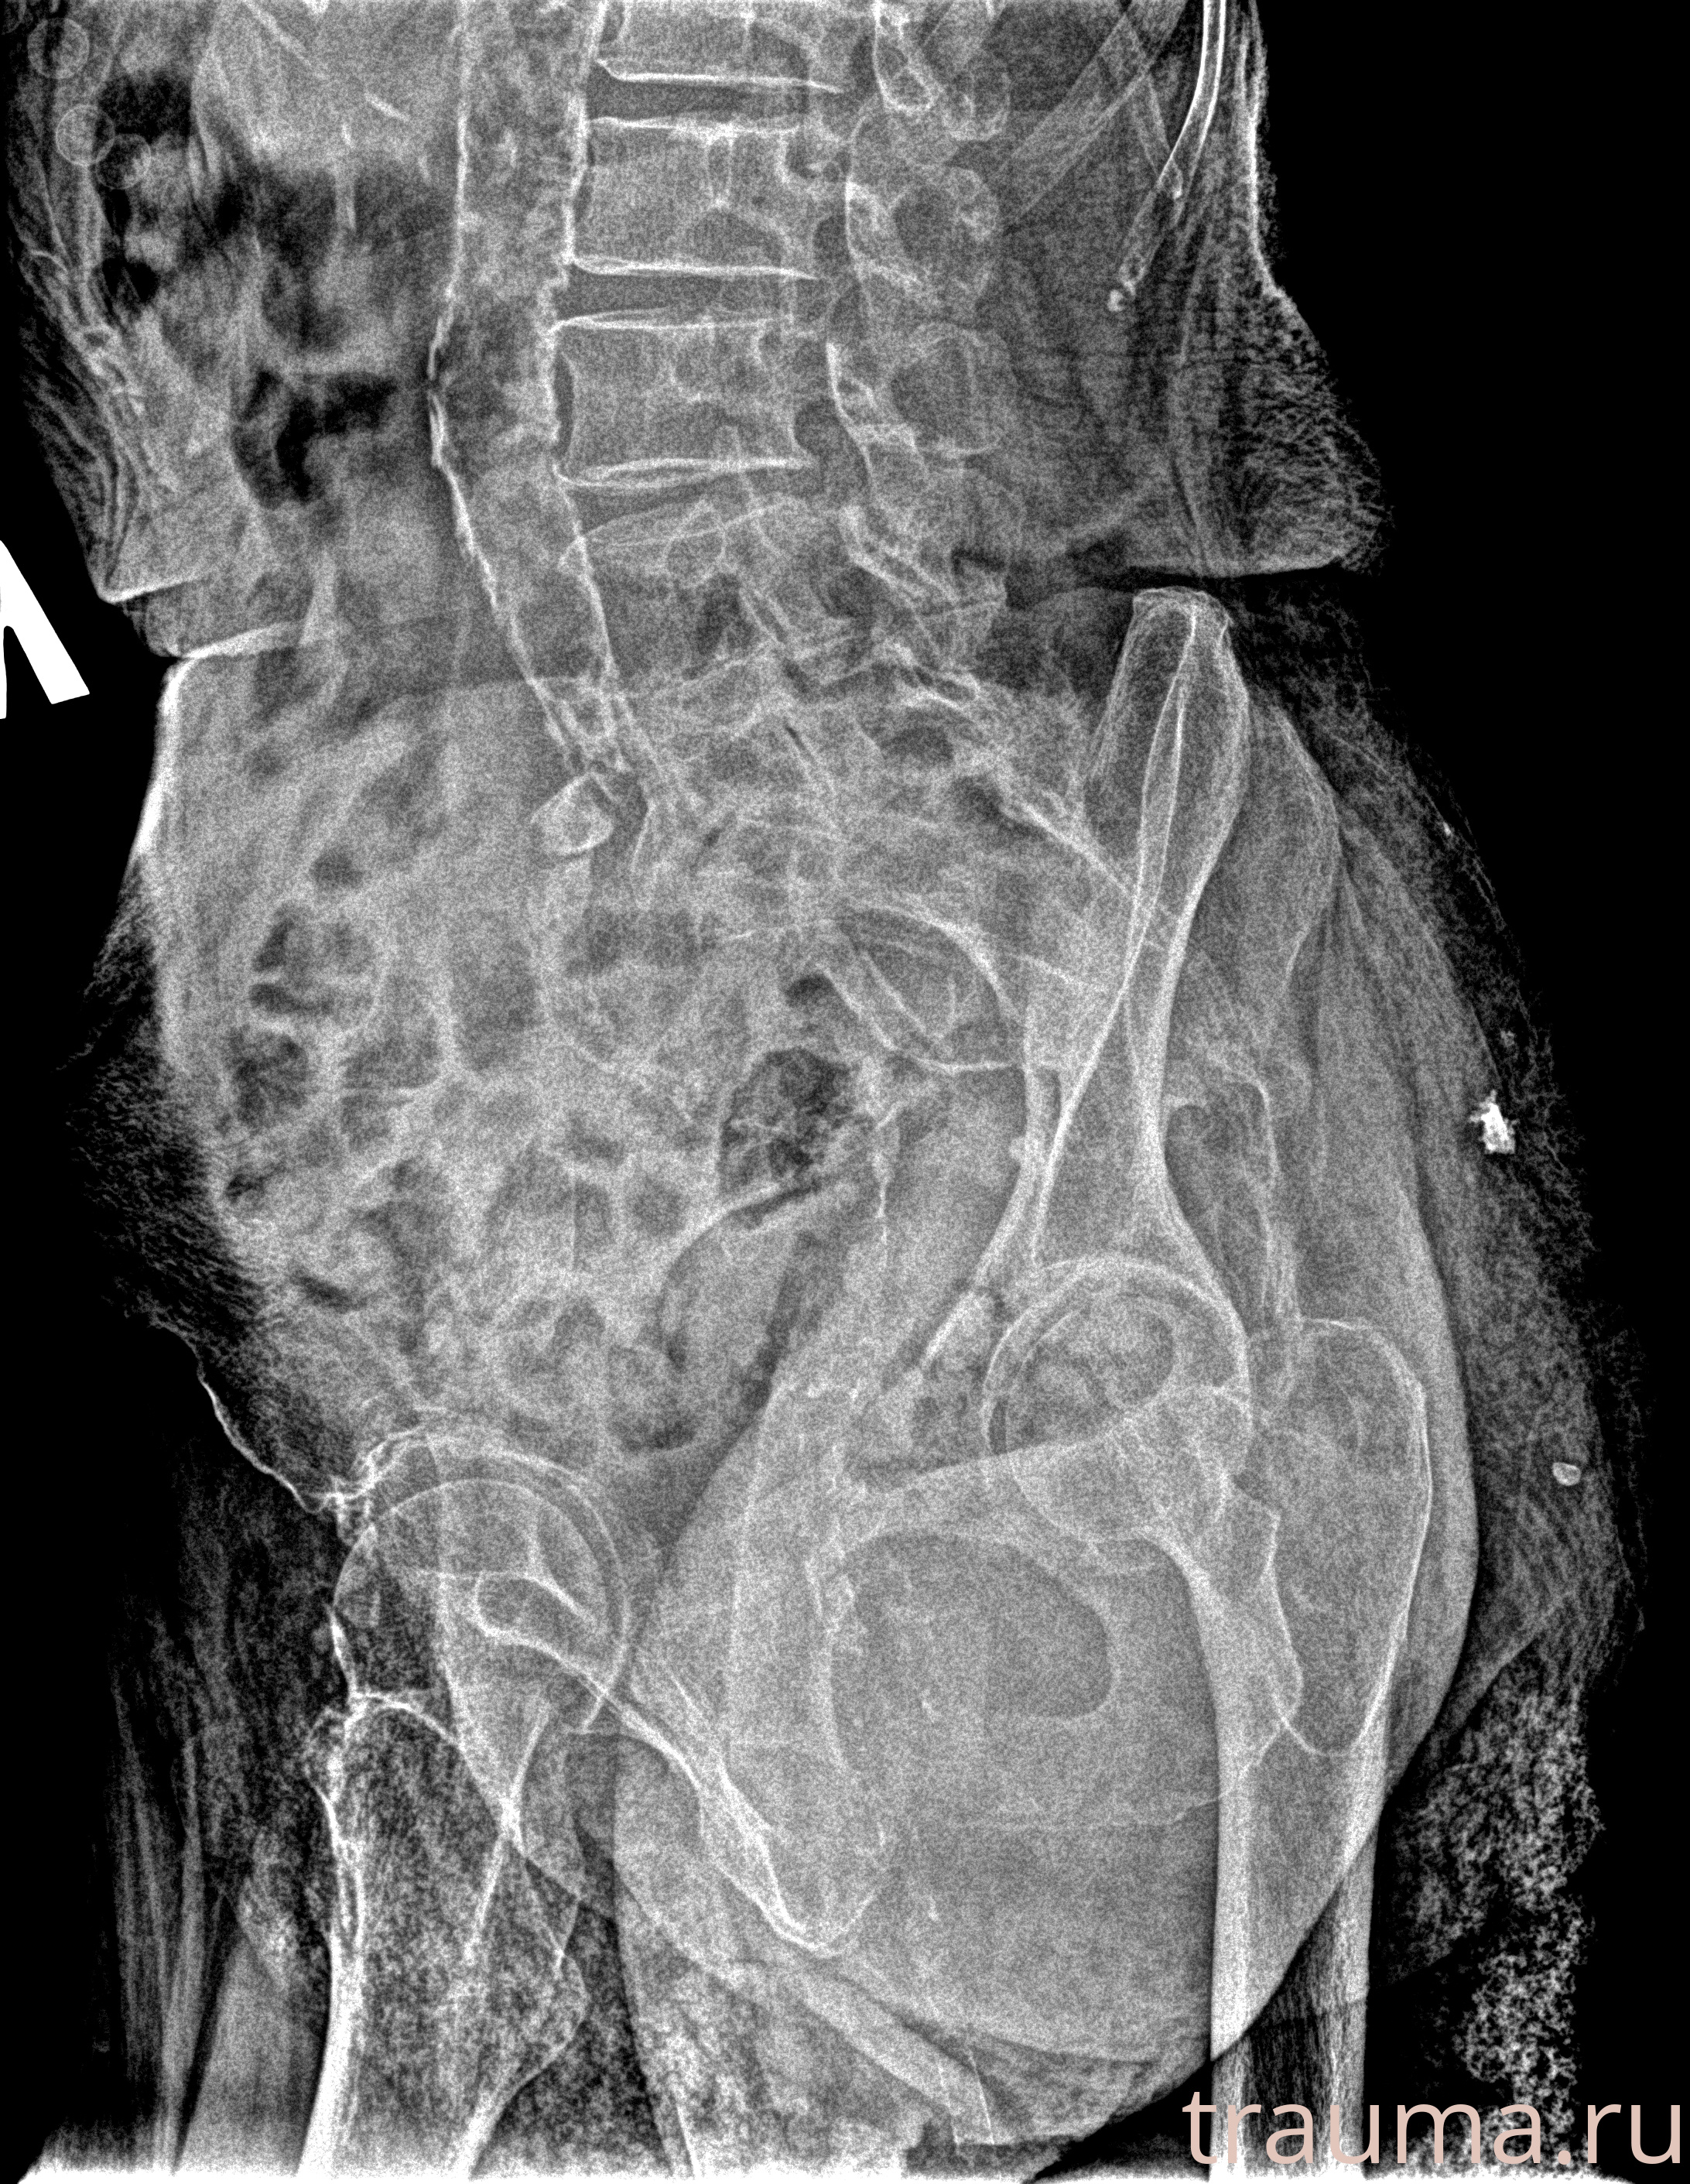

Рентген на дому: по вашему адресу приезжает врач-рентгенолог, травматолог-ортопед с мобильным рентгеновским аппаратом, проводит диагностику травмы или заболевания, делает необходимые рентгенограммы, дает рекомендации по дальнейшему лечению. Получить качественные снимки в домашних условиях возможно благодаря уникальной методике, разработанной МосРентген Центром для института  Склифосовского